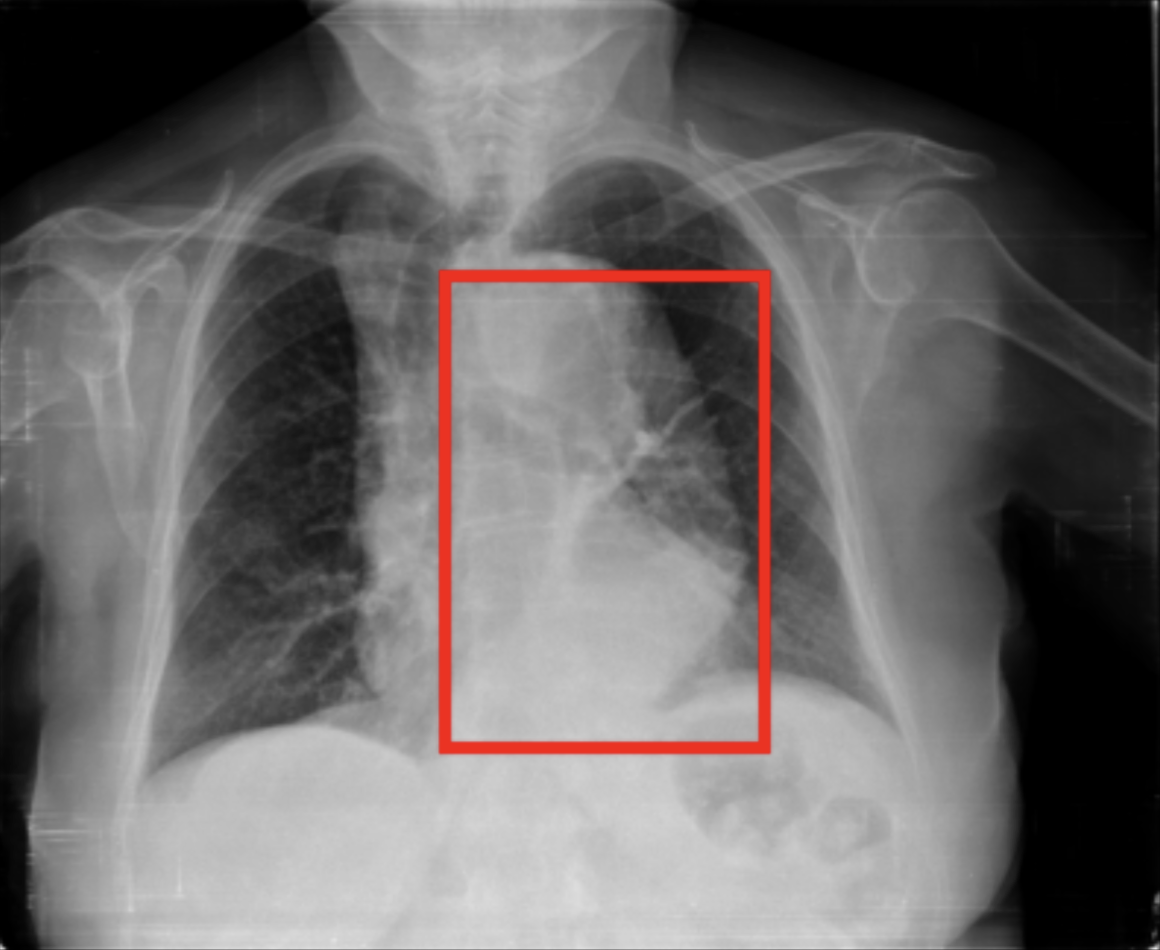

4.1.4 Multi-turn evaluation within conversational interactions

Evaluating conversational aspects of a model is essential to assess the utility and performance of an AI assistant in a multi-turn setting. We designed an LLM-based evaluation method carefully crafted for conversations, following the “LLM-as-judge” scheme (Zheng et al., 2023b, ) previously adopted by LLaVA-Med (Li et al., 2023a, ). We created a test set of conversations following our generation process (see Section 3.1.4). As a result, we obtained 155 conversations containing grounding questions (derived from MS-CXR test set), and 500 conversations without (Table 1).

During the evaluation process, we provide the CXR image to the VLM and sequentially ask the questions from this dataset. After collecting the VLM’s answer to each question, we prompt GPT-4o (text-only) with the CXR information (report, list of abnormalities, etc.), the expected answer per question (derived from the ground truth information), and the VLM-generated answer (see Appendix 1-Figure 2 for the prompt). At the end of the prompt, GPT-4o is asked to provide an overall score (from 0 to 10) for the quality and accuracy of generated answers as compared to ground truth. We report two scores: one based on the grounded conversations dataset and one based on the non-grounded (standard) one.

RadVLM’s instruction dataset also includes image-conversation pairs (Figure 2) generated with GPT-4o, by providing it with a radiology report, any available grounded phrases, and additional details. As mentioned in Section 4.1.4, we created two held-out evaluation sets using GPT-4o: one without grounded questions and one focused on grounded questions derived from the MS-CXR test set (Table 1). We run the evaluation on both test sets and report the average score across all samples. We also evaluate the other baseline models that possess conversational abilities, thoroughly respecting their prompting template within a multi-turn setting. The average GPT-4o scores for RadVLM and other models are gathered in Table 5.

Our results show that RadVLM, trained on a broad range of image-conversation pairs, achieves an average score of 6.66/10, substantially higher than the other conversational models, whose responses often prove incorrect or vague (Figure 6). This advantage may stem from RadVLM’s ability to handle varied question types and sequences in multi-turn exchanges, a skill reinforced by the sparse nature of its training conversations. The gap becomes even more pronounced in grounded scenarios, where RadVLM maintains strong performance (6.60/10) while others drop even more. Notably, this suggests that even the limited number of grounded conversations included (Table 1) was sufficient to equip RadVLM with robust grounding capabilities in a multi-turn setting.

| Model | GPT-4o Score | GPT-4o Score w/ grounding |

| LLaVA-OV | 3.66 | 2.95 |

| LLaVA-Med | 3.52 | 2.95 |

| RaDialog | 3.62 | 3.11 |

| RadVLM | 6.66 | 6.60 |

Overall score: <score>/10 Include no extra lines or text beyond this. Provided Data: • List of Abnormalities: Cardiomegaly, Lung Opacity, Pleural Other, Support Devices • Radiology report: There is a large amount of air (…) • View: AP • Gender: female • Selected observations with bounding boxes coordinates: – Moderate right pneumothorax: [0.19, 0.15, 0.51, 0.41] Conversation to Evaluate: • User: Can you tell me if this chest X-ray looks normal? Expected answer: The X-ray has several findings that appear abnormal, including air (…). Generated answer: The X-ray shows some findings that are not typical, including (…) • User: What does air in the pleural space mean? Expected answer: Air in the pleural space typically indicates what’s known (…) Generated answer: Air in the pleural space, known as a pneumothorax, means (…) Overall score: [score]